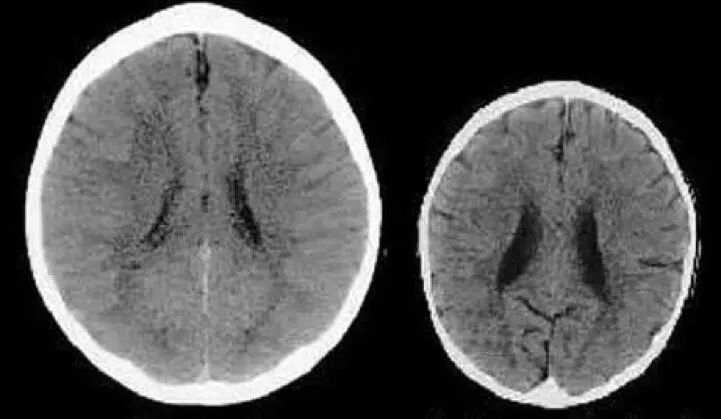

科学家曾经扫描过两个三岁孩子的大脑图形。

其中一个孩子的妈妈温柔善良,善于和孩子进行有效的沟通。而另一个孩子的妈妈非常冷漠,常常忽视孩子的需求,甚至虐待孩子。

两个孩子的大脑图形也是千差万别,如下图,左图是第一位孩子的(被温柔以待),右图是第二位孩子的(常被打骂)。

图片来源:Professer Bruce Perry

神经学家解释,右图的黑暗区域意味着大脑容量减少。缺失的区域使得孩子的成长过程中会缺乏智慧、同情心等能力。

由于长期遭受打骂,右边的孩子成年后有可能攻击性更强,自信心不足,事业拼搏力较差。

而左边的孩子,则明显相反。他包容、善良,长大后可能更容易成功。